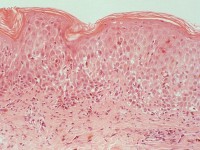

PA:In de beginfase een oppervlakkig perivasculair

neutrofiel infiltraat, later spongiose, necrotische keratinocyten en infiltraat

met lymfocyten en eosinofielen. Tevens pigmentincontinentie met melanofagen

in de papillaire dermis.

| prurigo

pigmentosa (PA) |

prurigo

Foto's: www.derm101.com.